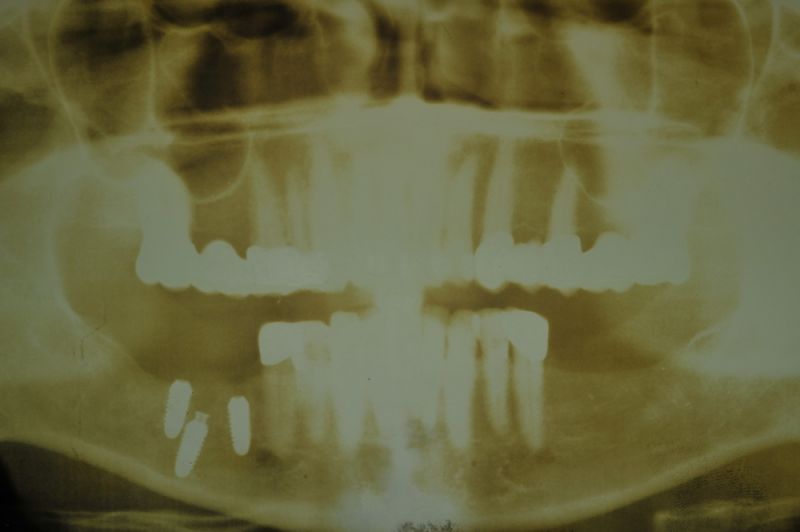

1. Notwendigkeit einer implantatgestützten Kronenversorgung mit der Vorgeschichte, dass die Patientin eine Vielzahl von Behandlern aufgesucht hatte, die eine Implantation im Unterkiefer als nicht durchführbar einschätzten.

2. Extrem schlechte knöcherne Verhältnisse im Unterkieferseitenzahnbereich, die sich intraoperativ noch einmal als ungünstiger darstellten, als bereits in den Voruntersuchungen erkennbar.

3. Sehr dünne Implantate, die von ursprünglich zwei je Kieferhälfte auf letztendlich drei je Kieferhälfte umgeplant werden mussten.